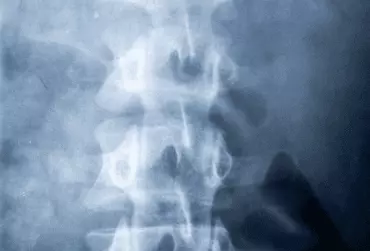

Skolioza idiopatyczna (SI) to strukturalna deformacja kręgosłupa o nieustalonej etiologii. W przypadku późnego wykrycia, a co za tym idzie – późnego włączenia leczenia może powodować szereg konsekwencji, takich jak pogorszenie estetyki ciała, zmniejszenie wydolności fizycznej i tolerancji wysiłkowej, częstsze bóle grzbietu czy poczucie niepełnosprawności. Celem niniejszego artykułu jest przedstawienie uzasadnienia dla prowadzenia badań przesiewowych mających pomóc we wczesnym wykryciu SI.

Skolioza idiopatyczna (SI) to trójpłaszczyznowa deformacja kręgosłupa, dla której na obecnym poziomie wiedzy nie znaleziono przyczyny [1]. Występuje ona u ok. 2–3% populacji i częściej dotyczy dziewcząt [2]. Skolioz idiopatycznych nie należy mylić z dość często występującymi u dzieci skoliozami funkcjonalnymi, które są zazwyczaj jednopłaszczyznowe i nie osiągają dużych wartości kątowych. Przedstawione w artykule rekomendacje dotyczą SI, która ze względu na nieustaloną etiologię, trójpłaszczyznowy charakter deformacji kręgosłupa oraz tendencję do progresji stanowi duże wyzwanie terapeutyczne [1, 3, 6].

Skolioza idiopatyczna to najbardziej rozpowszechniona postać skoliozy. Jak dotąd nie została poznana dokładna przyczyna tej deformacji kręgosłupa.

Skolioza idiopatyczna (SI) to trójpłaszczyznowa, strukturalna deformacja kręgosłupa, dla której na obecnym poziomie wiedzy nie znaleziono przyczyny [1]. Leczenie SI może być zachowawcze oraz operacyjne.